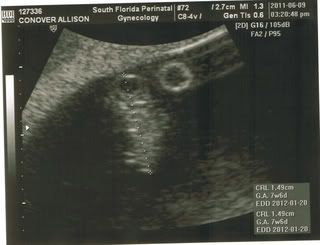

Little Raspberry

So yesterday was a big day. I went to the ultrasound appointment with low expectations for anything too exciting, but boy was I wrong! Our baby has more than doubled in size since the last appointment AND I got to hear his/her heartbeat!!! It was so exciting. I couldn't wipe the huge grin off my face. Our little raspberry's (apparently that's about how big he/she is) heart was beating so fast I could see it on the ultrasound. Brian was pretty disappointed he missed out, but he is planning to come to the next one July 11th.